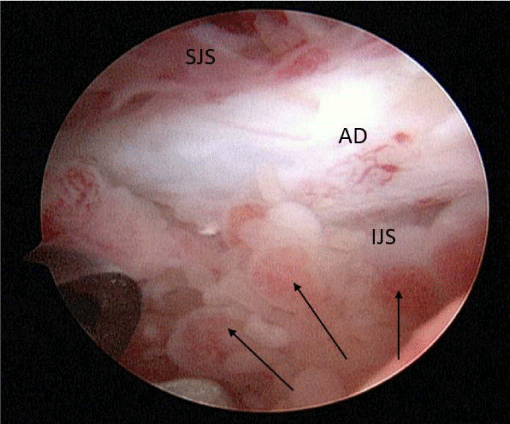

A 24-year-old female presented with a two-month history of right TMJ pain and locking. Examination revealed a 33mm mouth-opening with deviation to the right, bilateral mandibular condyles and right masseter tenderness to palpation, intact cranial nerves and no joint loading. There was no facial or preauricular swelling. The CT scan showed left greater than right condylar flattening with intact cortical outline and no osteolysis (Figure 1). The MRI showed bilaterally displaced discs with the left being deformed (Figure 2). The patient then underwent bilateral arthroscopy. Diagnostic arthroscopy on the left revealed synovial growth with striking reddish-orange discoloration. The disc was seemingly spared from the disease process (Figure 3,4). Synovectomy and debridement were completed. Histologic examination revealed PVNS (Figure 5). On her 10-month follow-up she reported significant improvement in pain and functional-limitation scores. She had a painless, symmetric 35mm mouth-opening with no joint tenderness or loading.